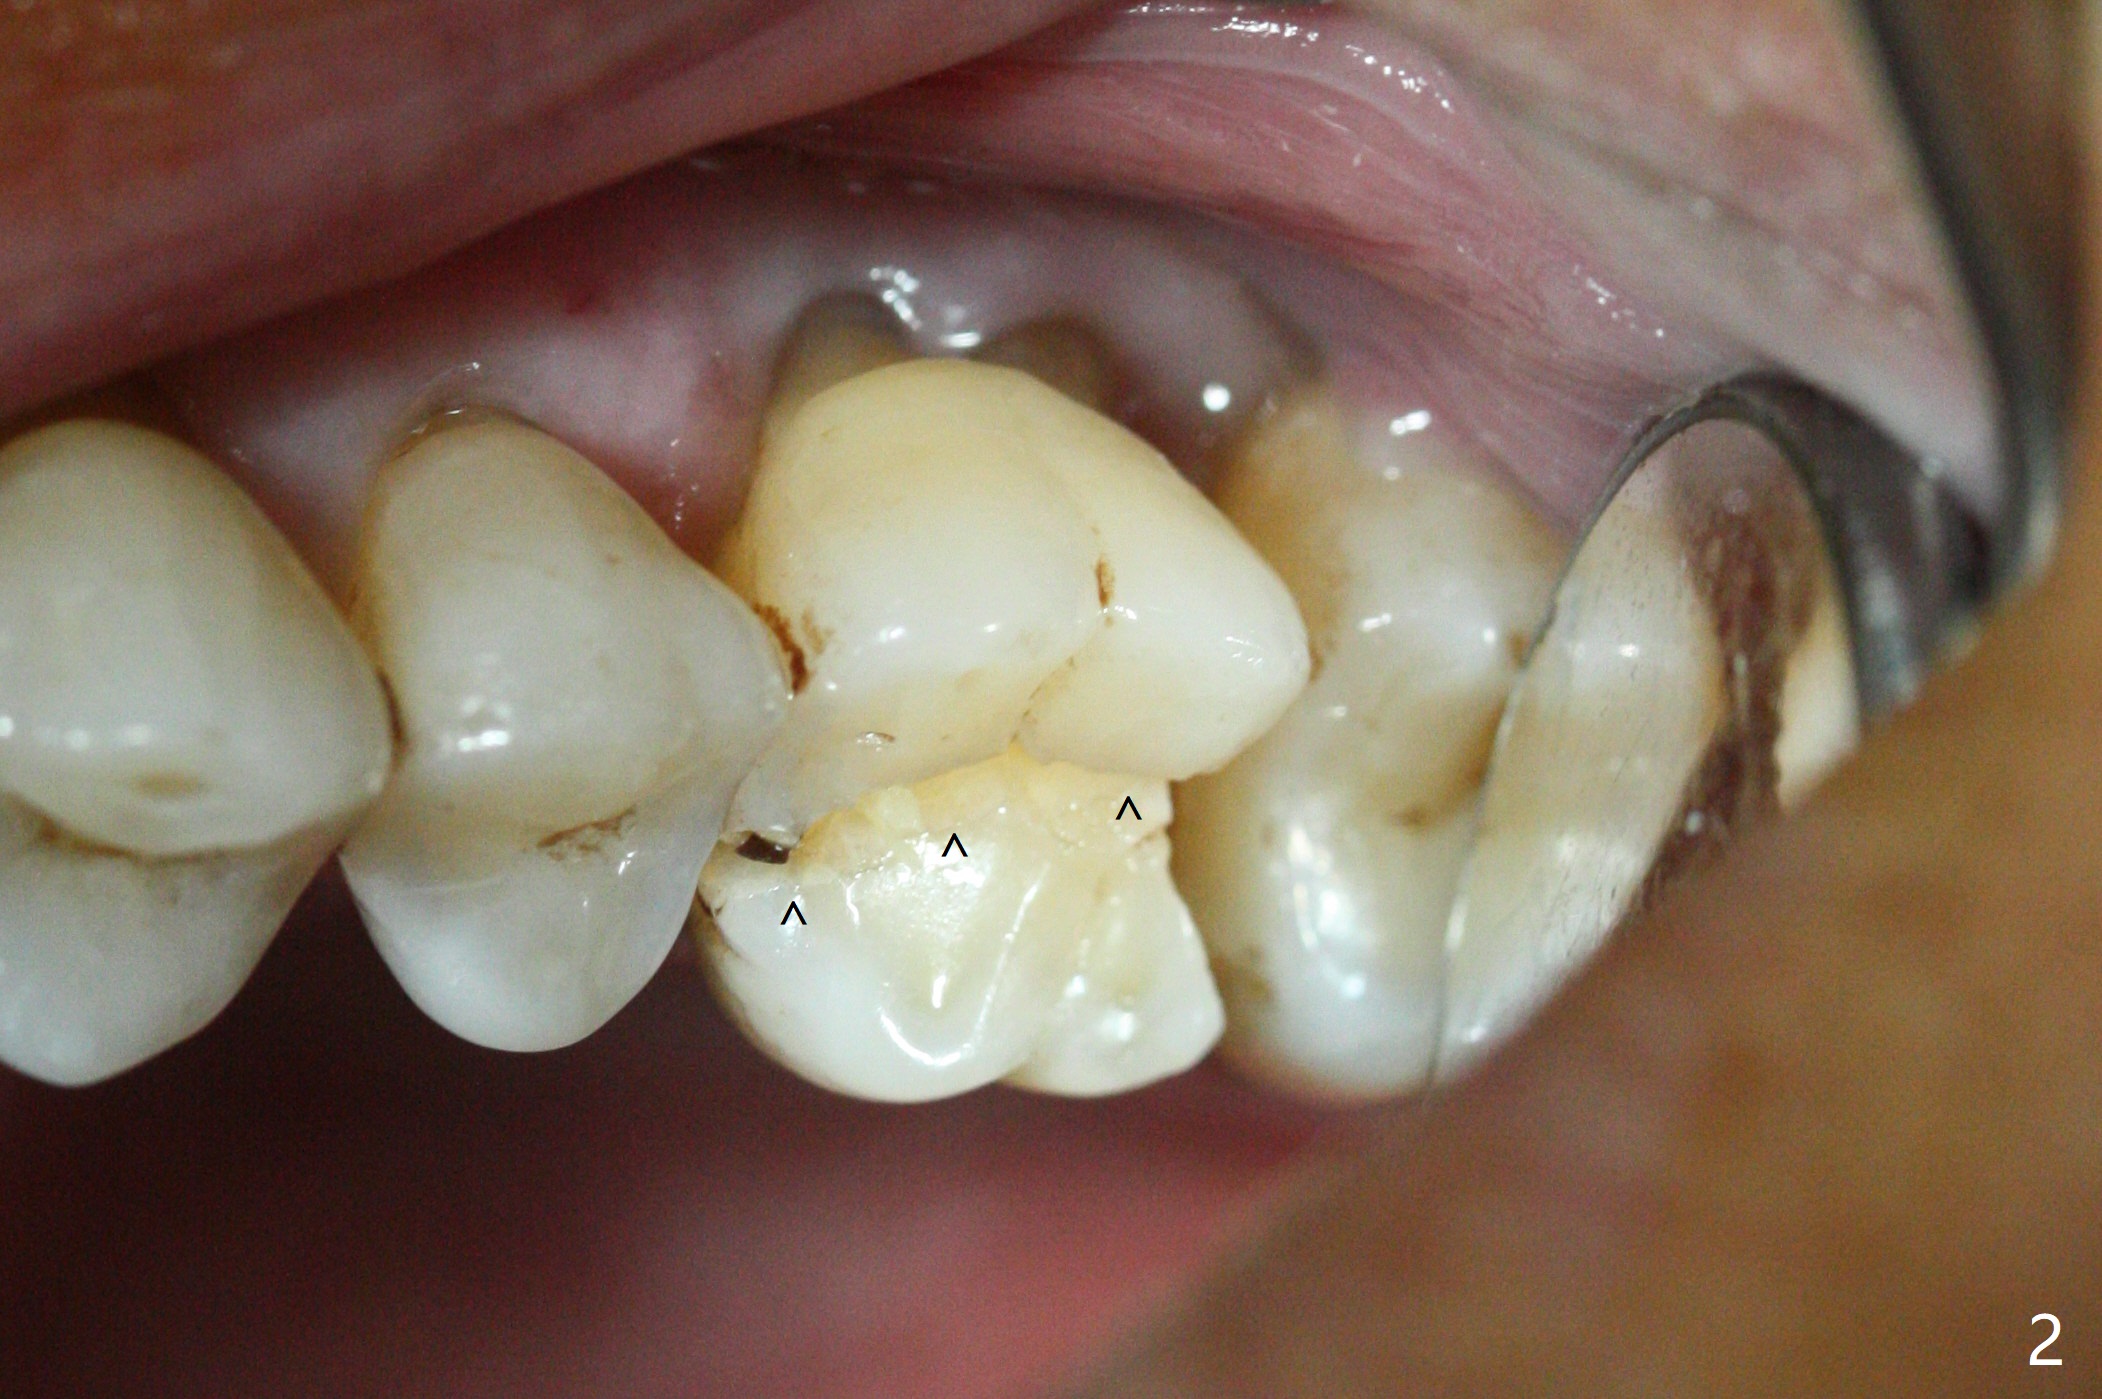

A 65-year-old man had crack tooth syndrome at #14 one month earlier (Fig.1). He shows up with crack and pain in an emergency manner (Fig.2 arrowheads). Preop CT confirms 4.5 mm bone height (Fig.3). Osteotomy will be initiated in the middle of the septum between 3 sockets (Fig.4). Depth of osteotomy is controlled with drill stoppers. After sequential osteotomy free hand, a 5x11 mm tap is used to break through the sinus floor (Fig.5) and sinus lift with Vanilla allograft. To prevent abutment screw loosening, a 5x11 mm tissue-level implant is placed; the distal thread is equicrestal (Fig.6 arrowhead). Following deeper placement of the implant (Fig.7 arrow) with a larger and longer abutment (as compared to that in Fig.6), the margin for an immediate provisional (Fig.9 white curved lines) is prepared in the coronal end of the implant (Fig.8 between arrowheads). With the tissue-level implant, the crown/implant ratio improves. Stress will be partially acting on the implant so that there is less likelihood of abutment screw loosening. The socket heals 1 month postop (Fig.10). The rough surface of the implant is exposed ~ 1 mm. With the margin modified and polished, the provisional returns to place with oral hygiene instruction. It is hoped that the gingiva will cover the exposed rough surface. The buccal rough surface remains exposed 5 months postop (Fig.11). The bone in sinus lift is mature 5 months postop (Fig.12,13). The first 1-2 implant threads are expected to be filled with mature bone in the near future (*). Since the abutment seems long enough for retention, temp bond is used for cementation (Fig.14). Water pik is being applied.